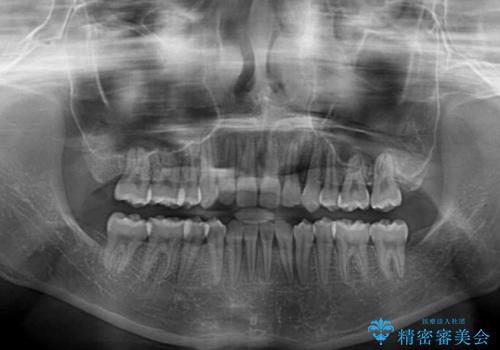

上顎左右第一小臼歯2本を抜歯し、ワイヤー装置にて矯正治療を行うこととしました。

通常の抜歯矯正と抜くべき歯の位置が異なるため、咬みにくさが残ってしまうのではないかと懸念されましたが、咬み合わせに違和感なく、スムーズに治療を終えることができました。